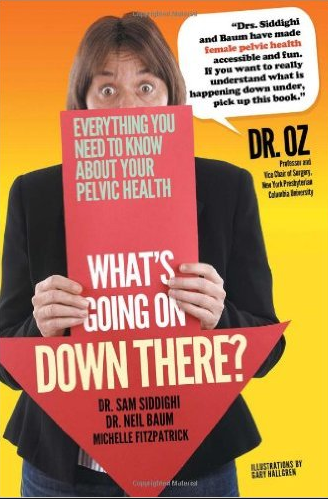

[Top]Book Review: What’s Going on Down There?

What’s Going on Down There? by Dr. Sam Siddighi, Dr. Neil Baurm, and Michelle Fitzpatrick is a detailed and simplified 304 paged book on women’s pelvic health. Women and physicians seldom divulge into pelvic health problems, which have led to countless women suffering from pelvic or vaginal reconstruction surgery related complications. To correct these complications, many women have resorted to filing mesh lawsuits as transvaginal mesh complications are among the most common. This book seeks to educate and empower women on pelvic health and thus help women understand and articulate their symptoms clearly. The book also offers useful tips on how women can improve their pelvic health.

The authors of the book are medical practitioners who are vastly experienced in women’s pelvic health. Therefore, their combined wealth of knowledge on the topic is hidden within the pages of this book. Additionally, the use of a jargon-free language that can be understood by virtually all women is a big plus. The authors took into account the prevalence of pelvic related complications among women aged 40 and above when writing the book. It is for this reason that it focuses on pelvic pain, urinary incontinence, premenstrual syndrome, vaginal prolapse among others. These complications are the number one cause of the many mesh lawsuits filed annually.

The primary goal of this book is to bring into the spotlight conditions and complications that are rarely talked about by women either due to embarrassment or lack of knowledge. Many women suffer in secret while others live with the illusion that they are fine. Unknown to some of these women there is a medical explanation for what is happening to them. Moreover, those who suffer in secret end up using huge chunks of money on diapers, pads and other such temporary remedies. For women to live comfortable lives and have a healthy pelvic area, understanding the functioning of their pelvic area is essential.

The book What’s Going on Down There? helps women understand the cause of their problems and also get medical assistance. The book demystifies the belief that aging is the cause of some of these conditions. Understanding the cause of these conditions is critical to their treatment. Thus, it is recommended for women to educate themselves on pelvic health to avoid some of these conditions and avoid being forced to file mesh lawsuits. For those who suffer from these conditions understanding their symptoms and treatment will be instrumental to them leading a pain-free life. Moreover, learning about pelvic health helps women make informed decisions about the kind of treatment that will suit them best.